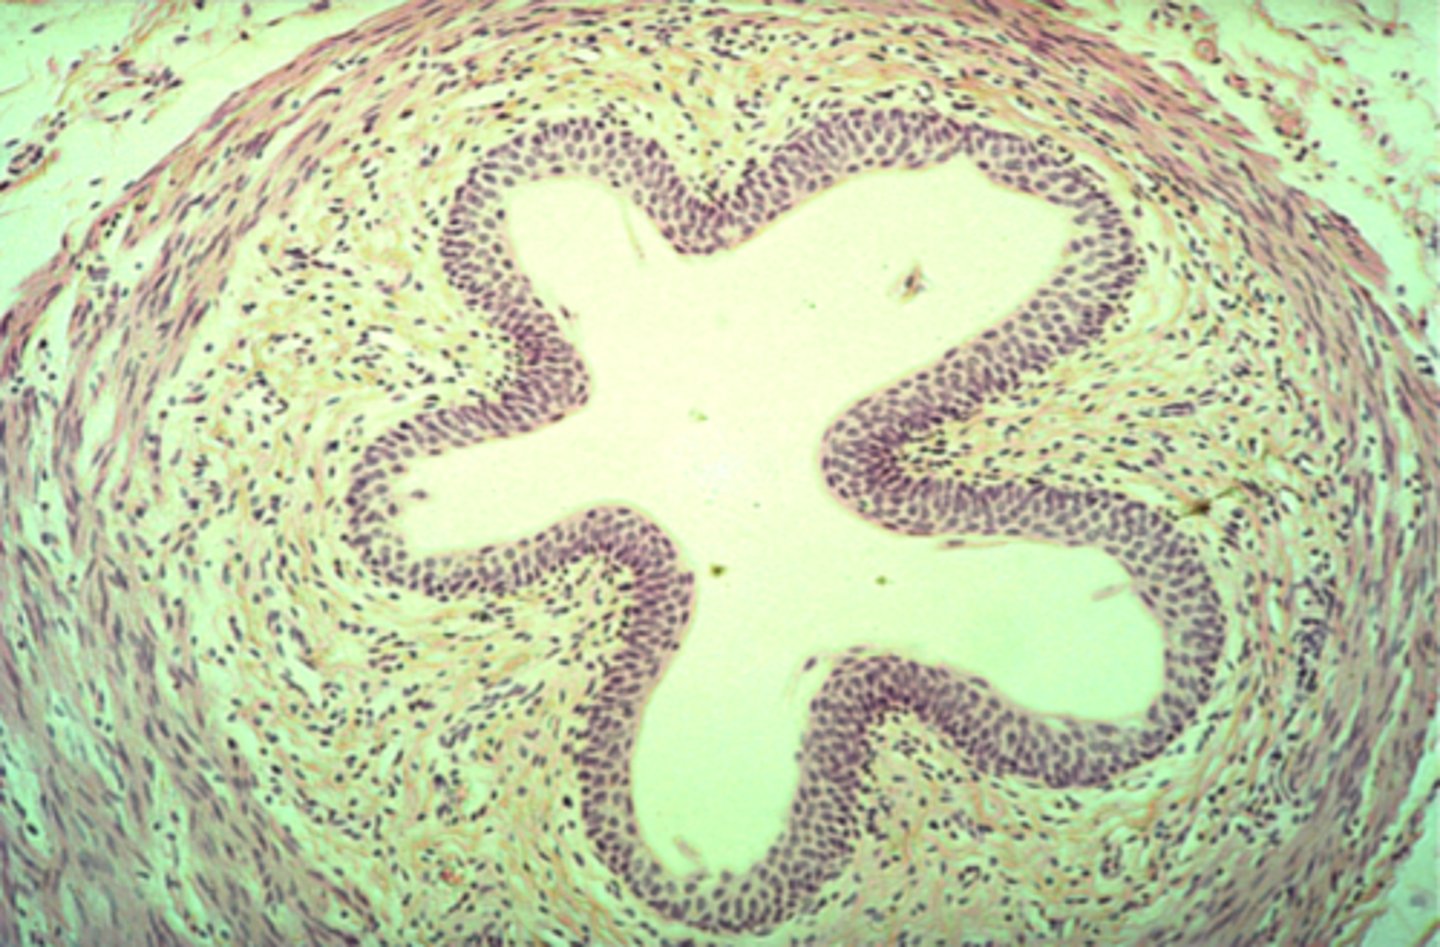

ureter

What is this?